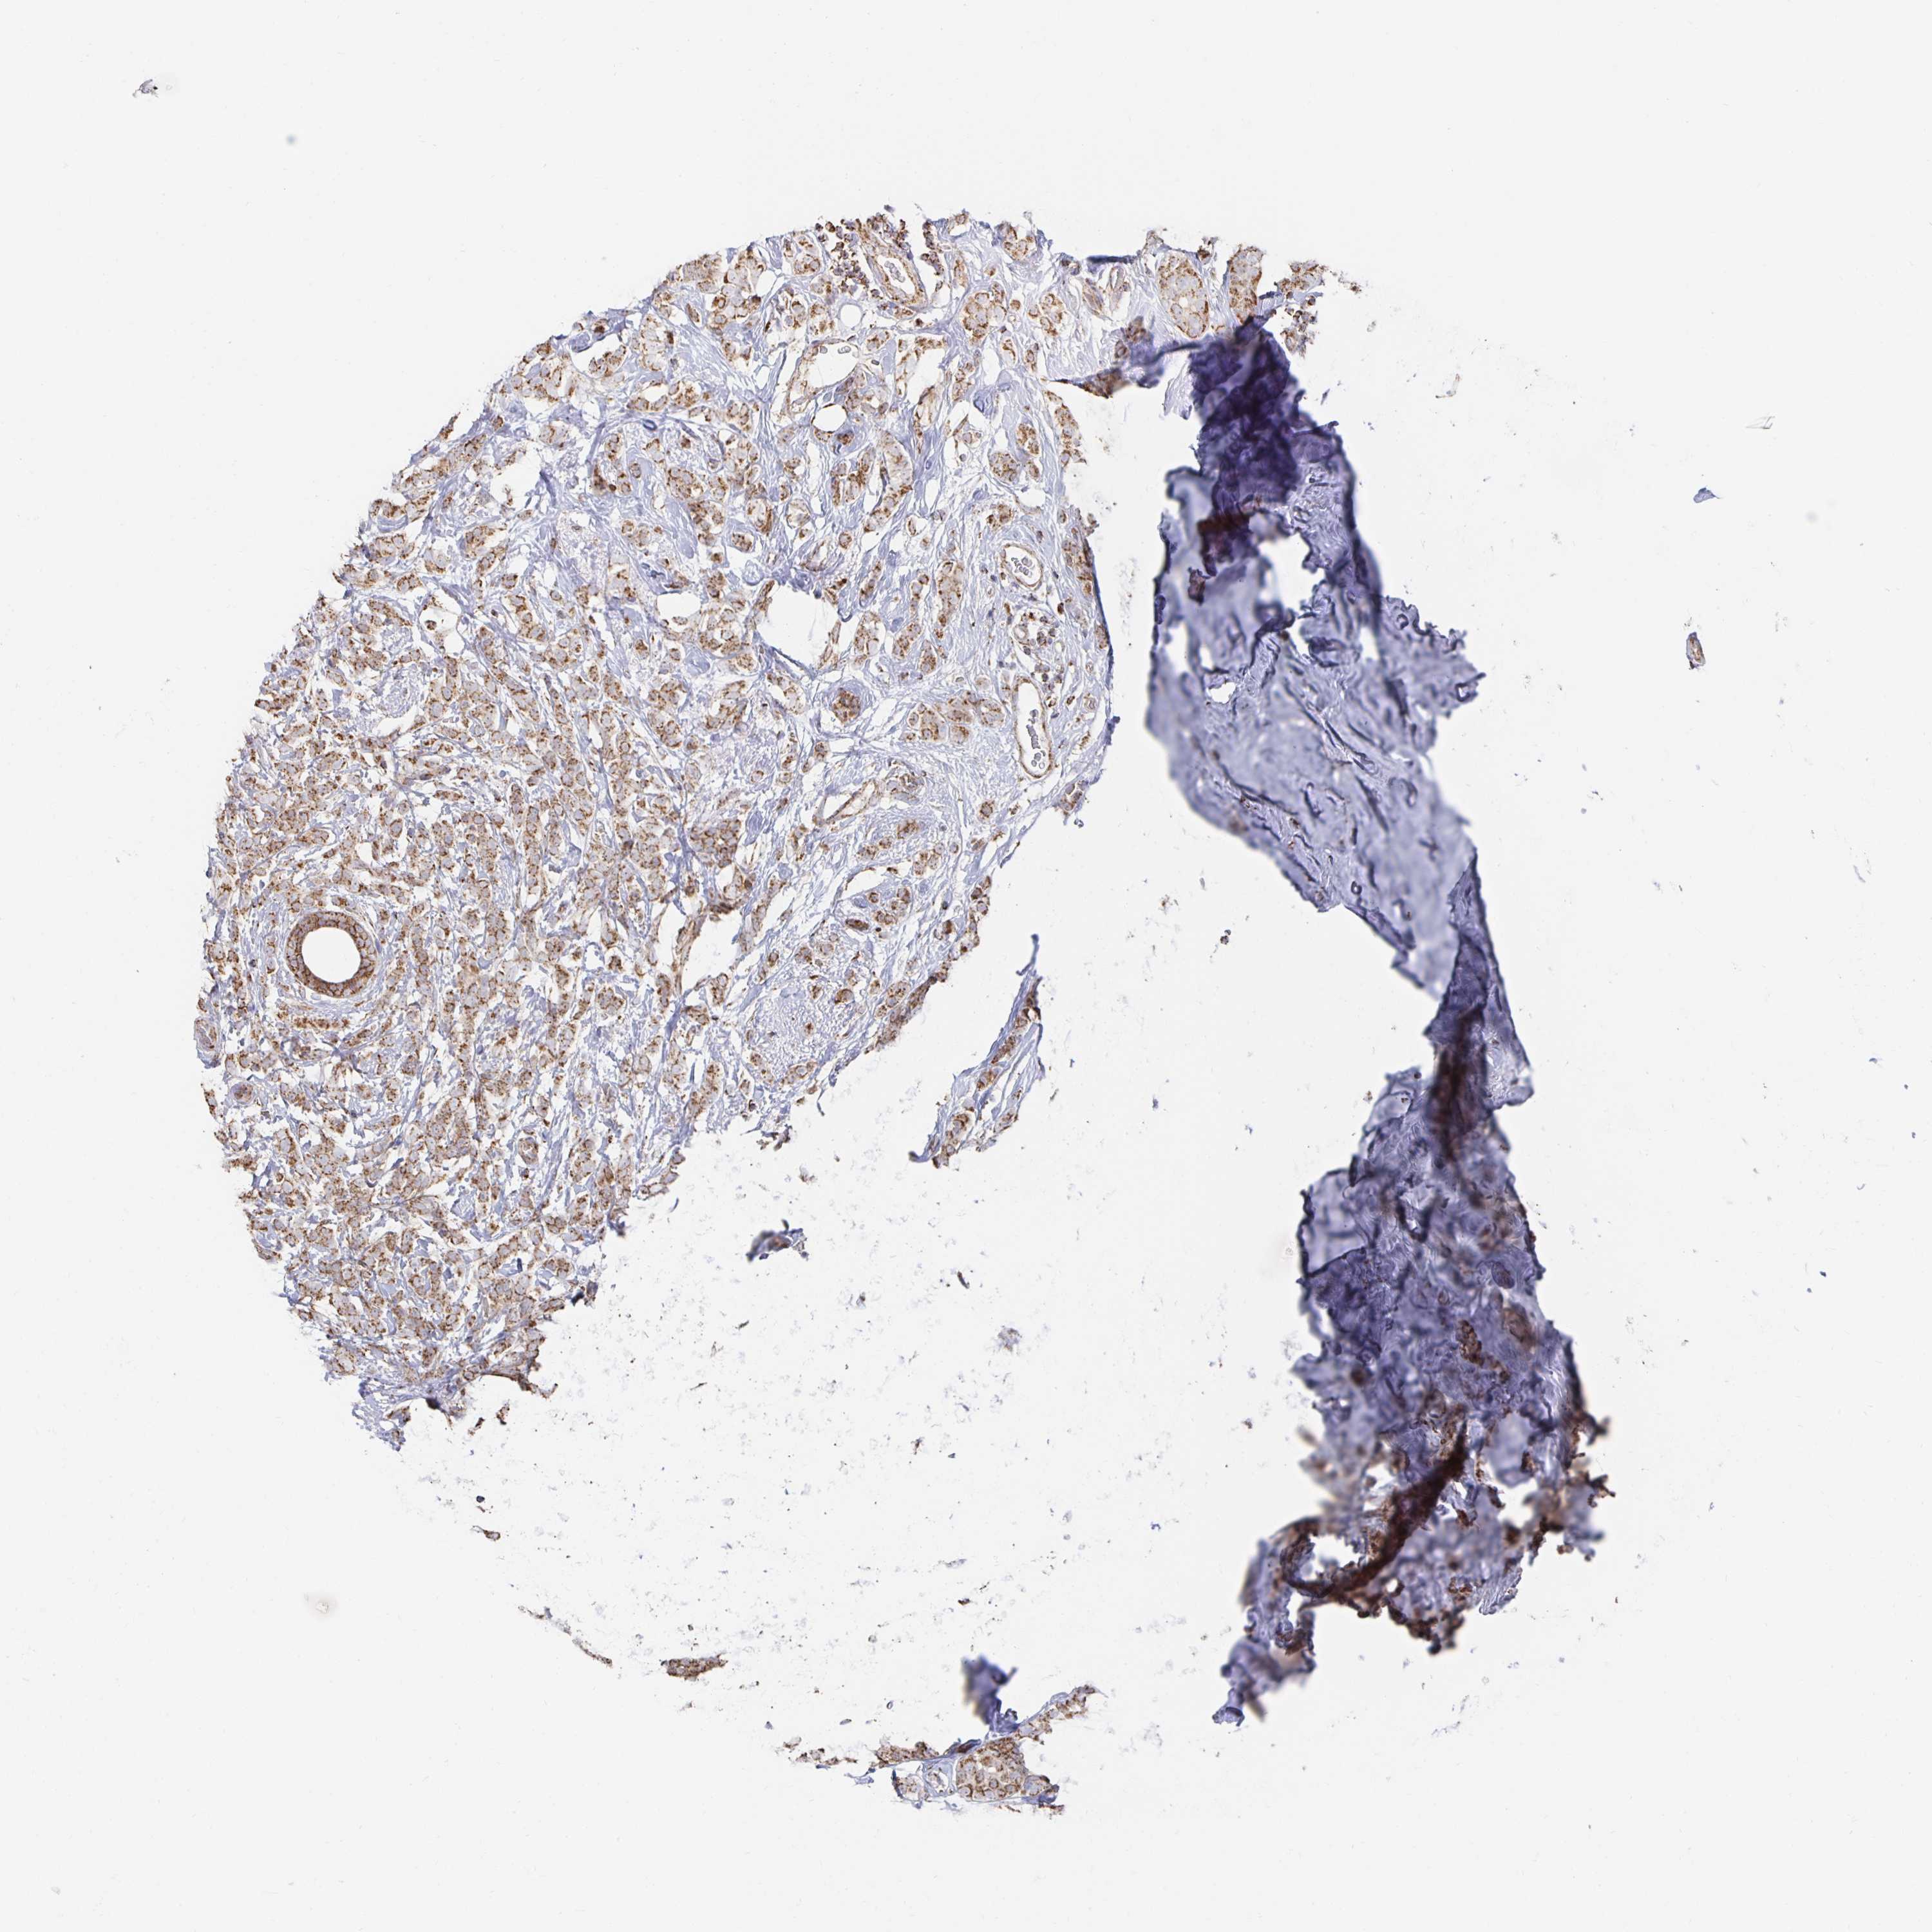

BRCA TCGA BRCA VALIDATION PROTEIN EXPRESSION

Breast cancer

Human cancer

Breast invasive carcinoma